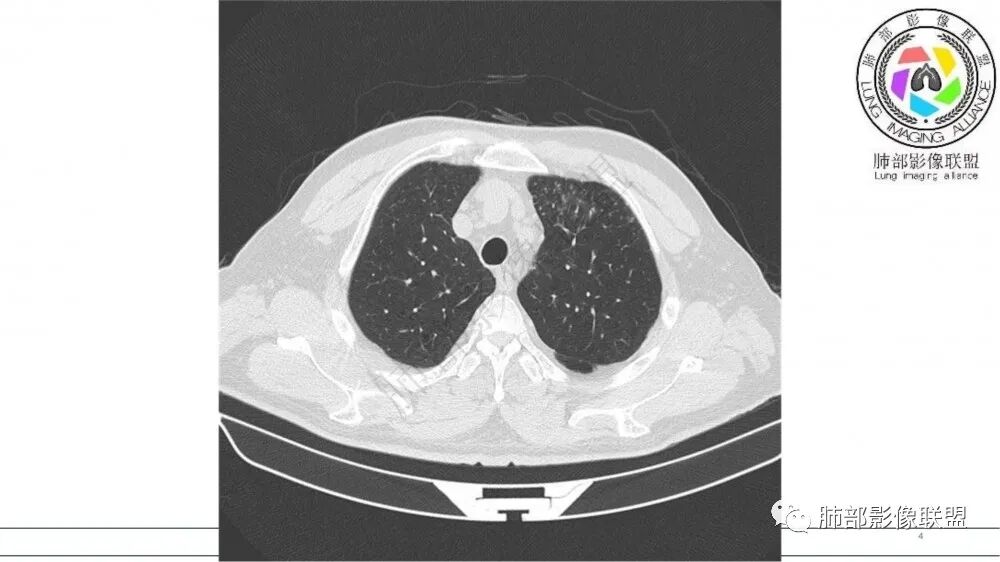

左肺上叶前段支气管杵状指样扩张,内见实性组织阻塞性,并强化明显,边缘饱满,周边多发小斑点影,小花小草征,老年男性,长期吸烟史,方向恶性,首选支气管内浸润鳞Ca可能性大。

老年男性,肺气肿,吸烟史,左肺上支气管腔内铸型高密度影,呈指套状,远端多发树芽,增强不均匀强化,考虑鳞癌,鉴别小细胞癌

小花小草,支气管阻塞,考虑鳞癌,鉴别腺癌,结核,及淋巴瘤

老年吸烟男,左肺上叶支气管堵塞,远端小花小草,纵隔未见肿大淋巴结,考虑鳞癌,建议进一步支气管镜检查

左肺上叶尖后段支气管近端截断,远端见高密度铸型,远侧见阻塞性改变,老年男性,吸烟史,考虑恶性,鳞癌。ABPA代排

指套征明确吧

有强化吧,淋巴结大

指套征,扩张支气管内软组织强化,远侧肺野阻塞性炎,纵隔、左肺门肿大淋巴结;老年男性,吸烟,考虑鳞癌,鉴别小

指套征:是影像征象,胸部平片表现为手指状密度增高影,以肺门为中心呈放射状分布,CT显示扩张支气管内低密度黏液栓形成或实性病变,呈管状、树枝状或卵圆形密度增高影;支气管扩张伴近端梗阻时,扩张支气管内部黏液分泌物不能排出而形成。可以伴随远端空气潴留征、阻塞性炎症。